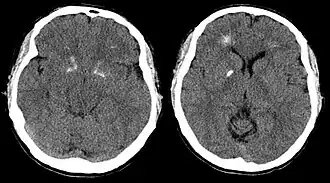

Компьютерная томограмма головного мозга пациента с синдромом Ди Георга демонстрирует кальцификацию базальных ганглиев и перивентрикулярное обызвествление. (По материалам Tonelli et al., 2007). | |